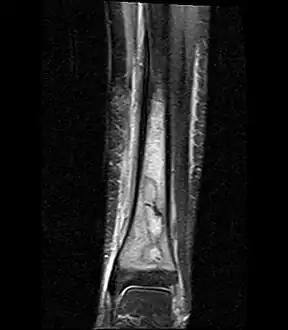

Fat saturated STIR (short tau inversion recovery) image showing hyperintense edema in the calf musculature, marrow edema, and subperiosteal pus. The intramedullary abscess cavity is hyperintense as well. -

Coronal fat suppressed STIR image showing, bone marrow and subcutaneous edema as well as subperiosteal edema. The thin hypointense rim surrounding the intramedullary collection represents the reactive interface between the abscess and the body's attempt to wall it off. -